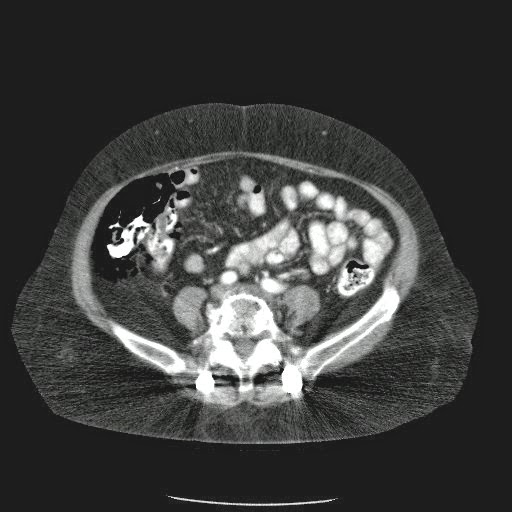

Paciente con antecedente de ALIF (Fusión lumbar intersomática anterior) 360 grados L5-S1 hace siete meses, quién presenta herida de abordaje anterior con dehiscencia de sutura, con cierre por segunda intención, quien consulta por cuadro clínico de dos días de secreción purulenta en herida quirúrgica, niega fiebre, niega otras sintomatología, refiere episodios previos similares.

Paciente en POP de ALIF L5-S1 quien presento dehiscencia de la herida abdominal con ISO superficial ya tratada, sin embargo persiste con dehiscencia y desde ayer con supuración asociado a fiebre subjetiva. Se realiza eco abdominal con colección en pared sugestiva de absceso, elevación de RFA por lo cual se considera se debe hospitalizar para manejo antibiótico, drenaje de la colección, manejo médico y vigilancia neurológica.

- ¿Hallazgos Escanografia?

2. Hay una colección de la pared abdominal en el flanco derecho, que realza en la periferia con el contraste, e intraabdominal tiene aire pero no me parece colección intraabdominal porque la grasa no está alterada.